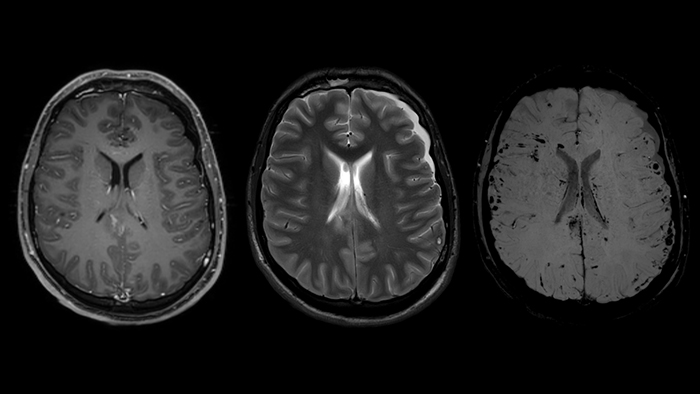

Магнитно-резонансная томография (МРТ) играет важную роль в диагностике неврологических заболеваний. Классические последовательности, применяемые в клинической практике, отражают такие ключевые параметры тканей, как: времена релаксации T1, T2 и T2*, измеряемый коэффициент диффузии и протонную плотность. Широко применяются последовательности, взвешенные по T1 и T2, инверсия-восстановление с подавлением воды (FLAIR) и диффузионная МРТ (рис. 1).

В настоящее время также активно развиваются методики для оценки магнитной восприимчивости, которая отражает содержание магнетиков в биологических тканях. К этим методам относятся изображения, взвешенные по магнитной восприимчивости (Susceptibility weighted imaging with phase enhancement, SWIp) и количественное картирование магнитной восприимчивости (Quantitative susceptibility mapping, QSM). Эти сравнительно новые типы взвешенности значительно отличаются от вышеупомянутых методик и обладают высокой чувствительностью к магнитной восприимчивости, даже по сравнению с последовательностями, взвешенными по T2* [1]. Количественное картирование магнитной восприимчивости чаще всего используется для определения содержания железа в базальных ганглиях на фоне нейродегенеративных заболеваний [2], в то время как изображения, взвешенные по магнитной восприимчивости, нашли более широкое клиническое применение при диффузно-аксональном повреждении головного мозга.

Умножение этой маски на магнитудное изображение никак не повлияет на области с положительной накопленной фазой, но повысит контрастность областей с повышенным содержанием парамагнитного железа. Конечный результат последовательности SWIp – SWI- и отфильтрованное фазовое изображение (рис. 6), обладающие уникальным контрастом, при этом первое отражает как локальные изменения магнитной восприимчивости тканей, так и значение амплитуды МР-сигнала. Таким образом, принципиальное преимущество метода SWIp по отношению к T2*-взвешенным изображениям - использование фазовых данных для повышения первоначального контраста магнитудных изображений. Это обуславливает более высокую диагностическую ценность этой методики по сравнению с T2* последовательностями [9].